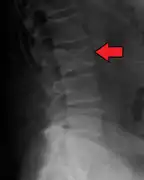

The diagnostic examination of a person with suspected multiple myeloma typically includes a skeletal survey. This is a series of X-rays of the skull, axial skeleton, and proximal long bones. Myeloma activity sometimes appears as "lytic lesions" (with local disappearance of normal bone due to resorption) or as "punched-out lesions" on the skull X-ray ("raindrop skull"). Lesions may also be sclerotic, which is seen as radiodense.[70] Overall, the radiodensity of myeloma is between −30 and 120 Hounsfield units (HU).[71] Magnetic resonance imaging is more sensitive than simple X-rays in the detection of lytic lesions, and may supersede a skeletal survey, especially when vertebral disease is suspected. Occasionally, a CT scan is performed to measure the size of soft-tissue plasmacytomas. Nuclear Medicine Bone scans are typically not of any additional value in the workup of people with myeloma (no new bone formation; lytic lesions not well visualized on nuclear bone scan).